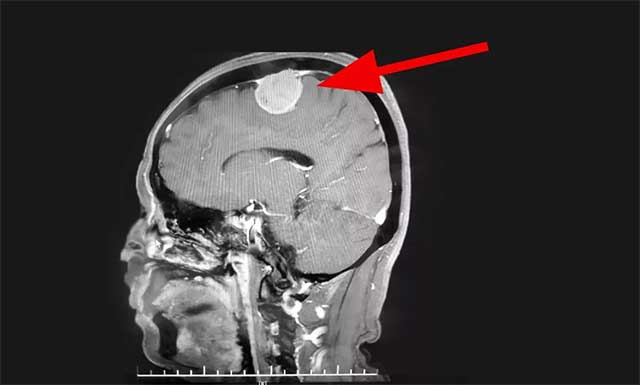

医院神经外科主任沈建康教授、神经外科6A病区侯增欣主任团队在对患者完善相关检查,并开展严谨的分析评估后认为:赵女士的肿瘤位于脑部重要功能区——中央前回附近,体积较大,占位效应明显,患者手术指征明确。在明确告知患者及家属手术风险并签字确认后,由沈建康教授主刀,为赵女士行肿瘤切除手术。

▲ 患者术前磁共振影像

术中可见,患者硬脑膜局部凸起,有明显肿瘤侵犯,硬膜动脉增粗。切开硬膜后,乒乓球大小(约4CM*4CM)的肿瘤呈灰白色,血运丰富。沈建康教授取瘤组织标本病理送检后,开始着手分块切除肿瘤。

在显微镜下,肿瘤自矢状窦向外生长,瘤体已包裹住了一支较大的皮层引流静脉。这条静脉非常重要,负责引流中央脑回的血流,必须完整保留。一旦损伤会引起静脉性水肿,严重的可导致灾难性后果——患者偏瘫甚至死亡。